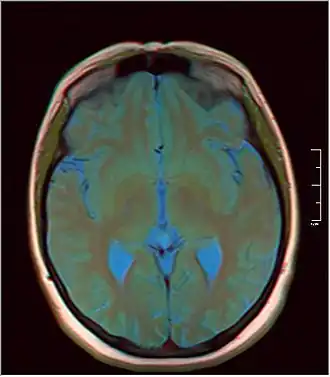

A pineal gland cyst is a usually benign (non-malignant) cyst in the pineal gland, a small endocrine gland in the brain. Historically, these fluid-filled bodies appeared on 1-4% of magnetic resonance imaging (MRI) brain scans, but were more frequently diagnosed at death, seen in 4-11% of autopsies.[1] A 2007 study by Pu et al. found a frequency of 23% in brain scans (with a mean diameter of 4.3 mm).[1]